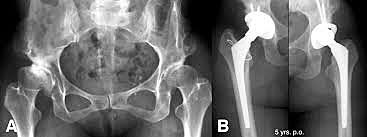

se comenzó a utilizar, sobre todo en Francia, componentes no

cementados por Judet y cols. en 1978 y por Lord y cols. en 1988,pero se observó la presencia de quistes semejantes (aunque

algo más pequeños), sobre todo alrededor del vástago femoral.